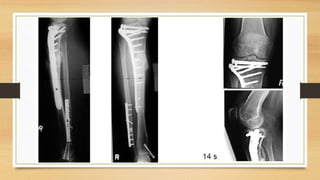

TTO POSOPERATORIO:

– Elevar la extremidad en una férula por 5 días o dispositivo de movilización pasiva

– Ortesis se retira cuando el paciente tiene control cuadricipital (7 – 10 día se consigue

una flexión de 90°).

– Fracturas tipo B o C permacen con carga parcial (10 – 15 Kg.) o sin carga, aproximadamente

de 6 – 8 semanas.

– Se permite mayor carga, hasta el 50% del peso corporal, después de las 6 – 8 semanas.

– Pacientes con fracturas de alta energía (lesiones B3 y C3) la carga total debe aplazarse 12 a 16

semanas.